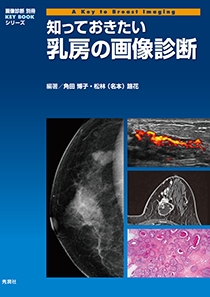

裁断済】乳房MRIアトラス | 在庫一掃 当店売れ筋!入荷。2025年最新】乳房MRIアトラスの人気アイテム - メルカリ。婦人科MRIアトラス 改訂第2版 (画像診断 別冊KEYBOOKシリーズ。淡路島。MRマンモグラフィにおける最新技術動向 - 東芝メディカル。m3電子書籍 | ACR BI-RADS®アトラス。コンパクト超音波neo 乳房アトラス【第4版】 | MediFlex。CT/MRI画像解剖ポケットアトラス 第3版 弟2巻 胸部・心臓・腹部。「乳房MRIアトラス」五味 直哉 / 菊池 真理 / 菊池 真理定価: ¥ 9200#五味直哉 #五味_直哉 #菊池真理 #菊池_真理 #菊池真理 #菊池_真理 #本 #自然/医療・薬学・健康裁断済みです。sd1_585584db08b281fb700be92614。•本文は書き込み、マーカーなく中身は状態良好です。無痛MRI乳がん検診 ドゥイブス・サーチ | 宇治徳洲会病院。切り口は揃っています。高松市乳がん個別検診実施医療機関】伊達病院 - 乳房MRIドック。•多少のキズや小さな角折れ等あるかもしれません。m3電子書籍 | ACR BI-RADS®アトラス。神経質な方は購入をお控えください。論文要約<乳房MRIで評価された腫瘍周囲領域の特徴と乳がんの。